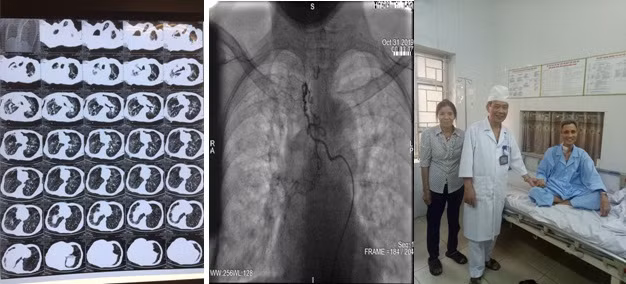

Các bác sĩ Trung tâm Nội Hô hấp, Bệnh viện Quân y 103 đã cấp cứu thành công một bệnh nhân nam 62 tuổi, ở Vĩnh Tường, Vĩnh Phúc, bị ho ra máu mức độ rất nặng.

Trước đó, bệnh nhân có tiền sử điều trị lao phổi 20 năm. Ba tháng gần đây bệnh nhân xuất hiện ho ra máu dai dẳng, ho máu tăng dần, mặc dù đã được điều trị nội khoa tích cực nhưng tình trạnh ho máu không thuyên giảm.

Bệnh nhân chuyển tới Trung tâm Nội Hô hấp, Bệnh viện Quân y 103 trong tình trạng thể trạng suy kiệt nặng (35kg/158cm), gù vẹo cột sống, 2 phổi bị xơ, giãn phế quản nặng.

Vào khoảng 22 giờ ngày 30/10/2019, bệnh nhân đột ngột ho máu số lượng khoảng 600ml màu đỏ tươi, biểu hiện suy hô hấp: tím tái, huyết áp tụt.

Các bác sĩ đã nhanh chóng khai thông đường thở, đặt ống nội khí quản, thở máy và ngay lập tức kích hoạt kíp trực can thiệp mạch cấp cứu. Sau 3 giờ can thiệp, bệnh nhân được chuyển về Trung tâm Hồi sức cấp cứu tiếp tục theo dõi. 2 ngày sau bệnh nhân được rút ống nội khí quản, ý thức và vận động hoàn toàn bình thường, bệnh nhân chỉ khạc ít đờm lẫn máu cũ.

Phó giáo sư, Tiến sĩ Mai Xuân Khẩn - Phó giám đốc Trung tâm Nội Hô hấp, người đã trực tiếp tham gia và chỉ đạo kíp cấp cứu nhận định, có thể nói đây là kỳ tích trong thực hành lâm sàng bởi lẽ bệnh nhân ho ra máu rất nặng tỷ lệ tử vong gần như 100% dù được cấp cứu kịp thời do tình trạng tắc nghẽn đường thở cấp tính nên được y văn gọi là "ho ra máu sét đánh".